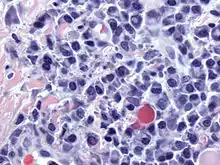

![]() خلايا بلازمية خبيثة (ورم الخلية البلازمية) مع النواة المميزة المظهر (كوجه الساعة) والتي ترى في الخلايا البلازمية الطبيعية. صبغة الهيماتوكسيلين والأيوزين. | |

الخلية البلازمية هي خلية لمفاوية كبيرة مع نسبة نووية سيتوبلاسمية عالية ومظهر مميز بالمجهر الضوئي. للخلية سيتوبلاسما أساسية ونواة لامركزية مع كروماتين كثيف بشكل مميز كعجلة العربة أو كتنسيق شكل الساعة. ويحتوي السيتوبلازم أيضا على منطقة شاحبة والتي أظهر المجهر الالكتروني احتواءها على جهاز جولجي كثيف وجسم مركزي (EM picture). إن وجود شبكة هيولية خشنة وافرة مع جهاز غولجي جيد التطور يجعل الخلايا البلازمية مناسبة جدا لإفراز الغلوبولينات المناعية [بحاجة لمصدر]. بقية الأعضاء في الخلية البلازمية تتضمن الريبوسومات -الليسوسومات - المتقدرات -الغشاء السيتوبلازمي.

إن ورم الخلايا البلازمية والورم النقوي العديد وداء والدنستروم لفرط الغلوبولينات المناعية الكبرى والابيضاض بالخلية البلازمية هي تنشؤات خبيثة (سرطانات) للخلايا البلازمية[11]. يتميز الورم النقوي العديد عادة بإفراز أضداد يمكن تحديدها كبارا بروتينات. ويعود نقص المناعة الشائع المتفاوت إلى مشكلة في التمايز من لمفاويات إلى خلايا بلازمية والنتيجة مستوى أضداد مصلية قليل وخطورة الإصابة بالأخماج.